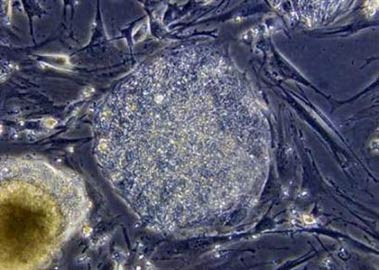

A microscopic view of undifferentiated human

embryonic stem cells. California Gov. Arnold Schwarzenegger moved on